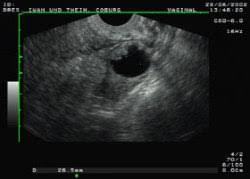

Die Ultraschalluntersuchung Sonografie ist meist die erste bildgebende Untersuchung bei Verdacht auf Blasenkrebs. Die Klassifikation Stadieneinteilung oder Staging genannt ist ein wichtiger Baustein für die Wahl der optimalen Therapie. Dabei kann der Arzt Blase Nieren und Harnwege begutachten.

Dr Neumeister Und Dr Thein Coburg

Eine Ultraschalluntersuchung ermöglicht auch Blasensteine oder einen Blasentumor zu entdecken. Wirken Lymphknoten verdächtig veranlassen Ärzte in der Regel eine Biopsie oder Lymphknotenentnahme. Per Ultraschall lassen sich auch mögliche andere Ursachen für Beschwerden erkennen beispielsweise Nieren- Blasen-. Blasenkrebs kann als Folge einer Strahlentherapie entstehen. Blasenkrebs Mit der Diagnose Blasenkrebs hat der Patient nicht gerechnet. Sofern der Verdacht auf Blasenkrebs besteht nimmt der Arzt eine gründliche Untersuchung vor. Sie stellt zusammen mit der Biopsie Gewebeprobeentnahme die wichtigste Untersuchung für die Diagnose von Blasenkrebs dar. Ziel der Diagnostik ist eine möglichst frühzeitige Diagnosestellung und die Erhärtung oder Ausräumung des Verdachts auf Blasenkrebs. So stellen Ärzte beispielsweise bei Patienten mit einem Gebärmuttertumor ein erhöhtes Risiko für.

Die wichtigste Untersuchung zur Diagnose-Stellung ist die Spiegelung der Harnblase die sogenannte Zystoskopie. Es gibt keine Tumormarker im Blut die spezifisch für Blasenkrebs sind. Per Tastuntersuchung nimmt er dabei die Nierengegend den Unterbauch und die Geschlechtsorgane unter die Lupe. Blasenkrebs Mit der Diagnose Blasenkrebs hat der Patient nicht gerechnet. Liegt ein invasiver Harnblasentumor vor sind tiefgreifende Maßnahmen nötig. Wirken Lymphknoten verdächtig veranlassen Ärzte in der Regel eine Biopsie oder Lymphknotenentnahme. Die Ultraschalluntersuchung Sonografie ist meist die erste bildgebende Untersuchung bei Verdacht auf Blasenkrebs.